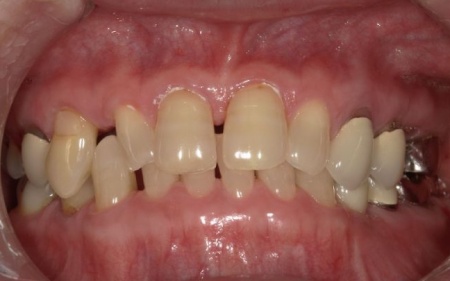

70代女性 歯根が割れた左下奥歯を抜きインプラントで噛み合わせを回復させた症例

「噛んだときに左下奥歯が痛むので診てほしい」とご相談いただきました。

レントゲン撮影を行って詳しく拝見したところ、左下奥歯(第1小臼歯)の歯根が割れていました。

それぞれのメリットとデメリットを説明したところ、患者様は①のインプラント治療を希望されました。

まず、周辺組織に負担をかけないよう配慮しながら、慎重に左下奥歯(第1小臼歯)を抜きます。

抜歯後は骨や歯茎の回復を待ち、口腔内の状態が安定したことを確認して、インプラント埋入手術へ進みました。

後日、インプラントと骨がしっかりと結合したら、精密な型取りを行い、被せ物を作製します。

最後に完成した被せ物を装着し、痛みや違和感がないか、見た目や噛み合わせに問題がないかを確認して、治療を終了しました。